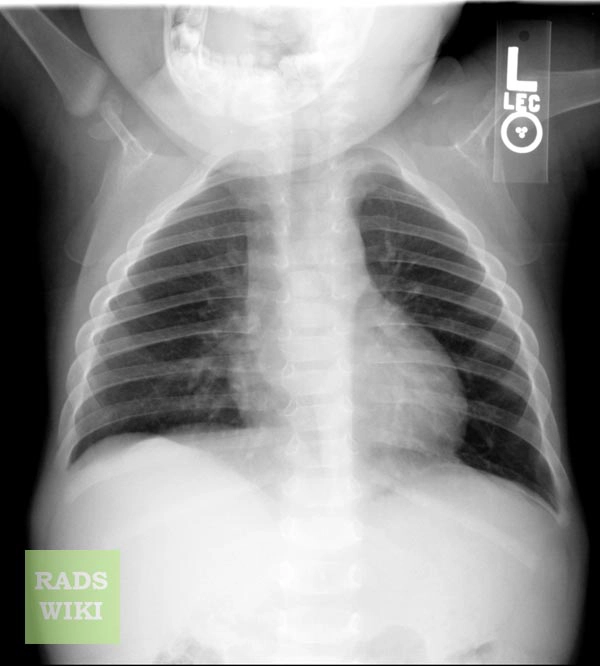

Bệnh tăng vỏ xương ở trẻ sơ sinh (Infantile cortical hyperostosis)/ Bệnh Caffery

16/03/2026